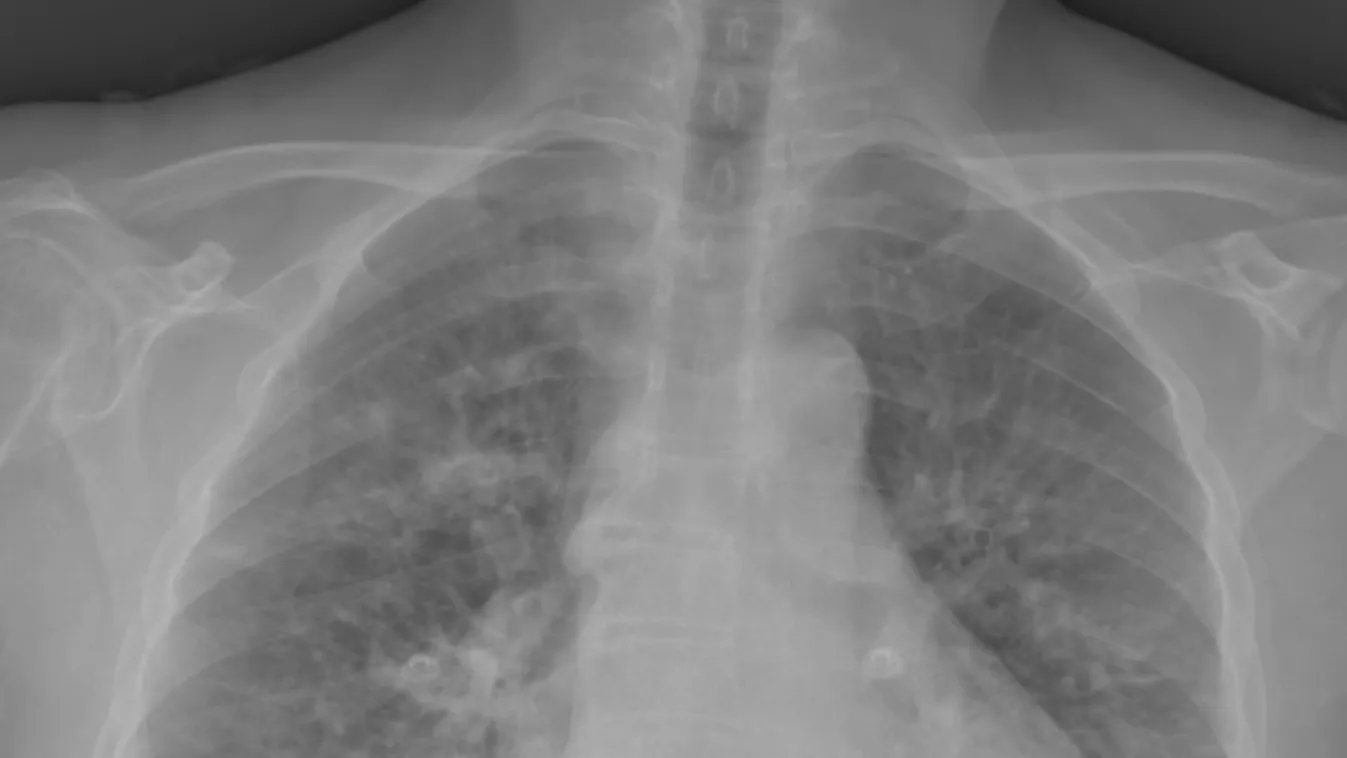

Akik a fertőzésből történt felépülés után még mindig légszomjat, erős fáradékonyságot, heves szívverés érzést, alvászavart, szédülékenységet, tartósan nem múló ízlés- és szaglászavart vagy -vesztést tapasztalnak, feltehetően poszt-COVID szindrómában szenvednek.

A fennmaradó vagy visszatérően erősödő légúti, szív- és érrendszeri, véralvadási, idegrendszeri, mozgásszervi, pszichiátriai, emésztőrendszeri, fül-orr-gégészeti vagy bőrgyógyászati problémák akadályozzák a betegek megszokott életvitelét és a munkába való visszatérést.